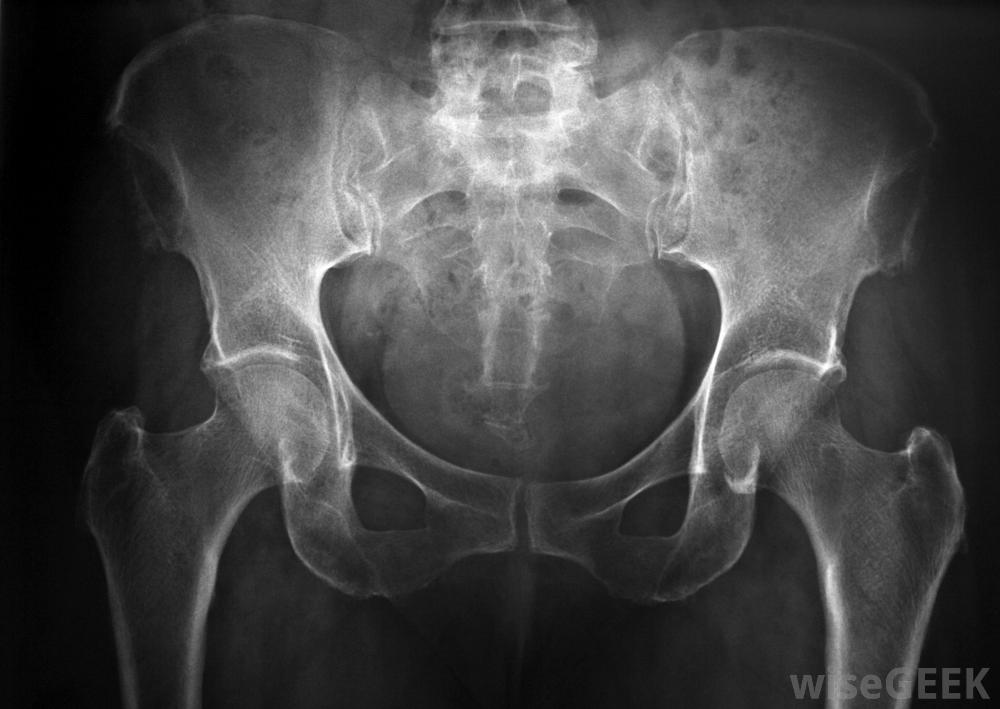

陰部神經病變是一種疼痛性疾病,影響骨盆下部的陰部神經。如果主神經或其分支受到擠壓、損傷或發炎,則會引起生殖器和直腸的劇痛和其他癥狀。陰部神經病變通常是由該部位的嚴重創傷引起的,但是,如果一個人不斷地對該區域施加壓力,也會產生問題,就像每天騎自行車一樣。治療取決于癥狀的嚴重程度,患者可能需要服藥、接受物理治療或接受手術來緩解癥狀如果醫生懷疑陰部神經病變,x光可以用來尋找受損的組織和神經。許多陰部神經病變的病例都是由外傷引起的,在這種情況下,腹股溝和肛門受到了很大的壓力。自行車撞車,摔倒在柵欄上,或分娩特別困難都是可能的原因。在某些情況下,由于過度勞累,神經壓迫會隨著時間的推移逐漸發生。熱衷騎自行車的人患慢性陰部神經病變的風險特別高。如果骨盆手術引起廣泛腫脹或陰部神經意外受損,骨盆手術也可能導致神經病變骨盆疼痛可能是陰部神經病變的癥狀陰部神經病變最常見的癥狀是外生殖器、肛門或兩者之間的尖銳刺痛。當坐下來或觸摸該部位時,疼痛通常會加重。一個人也可能會出現排尿或排便困難、疼痛或灼熱感。一些男性和女性也會出現性功能障礙,例如無法被喚醒或生殖器的敏感度明顯降低。許多陰部神經病變的病例都是由腹股溝區緊張引起的醫生在檢查病人的癥狀和進行快速體檢后可能會懷疑陰部神經病變。通常會進行X光和計算機斷層掃描,以尋找骨盆中受損的組織和神經,如果不清楚的話問題在于,可能會沿著神經中的可疑部位注射局部麻醉劑,看看疼痛是否減輕。醫生根據位置、性質和,陰部神經病變的嚴重程度。陰部神經病變可由分娩特別困難引起有輕微癥狀的人通常可以通過休息和服用非處方止痛藥來恢復建議在幾周后進行盆底運動,以逐漸增強骨盆肌肉的力量和彈性。如果疼痛嚴重,患者可能需要注射類固醇以暫時緩解炎癥和疼痛。只有在癥狀經常復發或無法恢復時,才需要手術減壓陰部神經通過醫療護理和鍛煉更好。通過醫學影像掃描仔細檢查骨盆,以確定疼痛原因患有陰部神經病變的人在排尿時可能會出現灼燒感。經常騎自行車的人患上慢性陰部疼痛的風險很高神經病。。